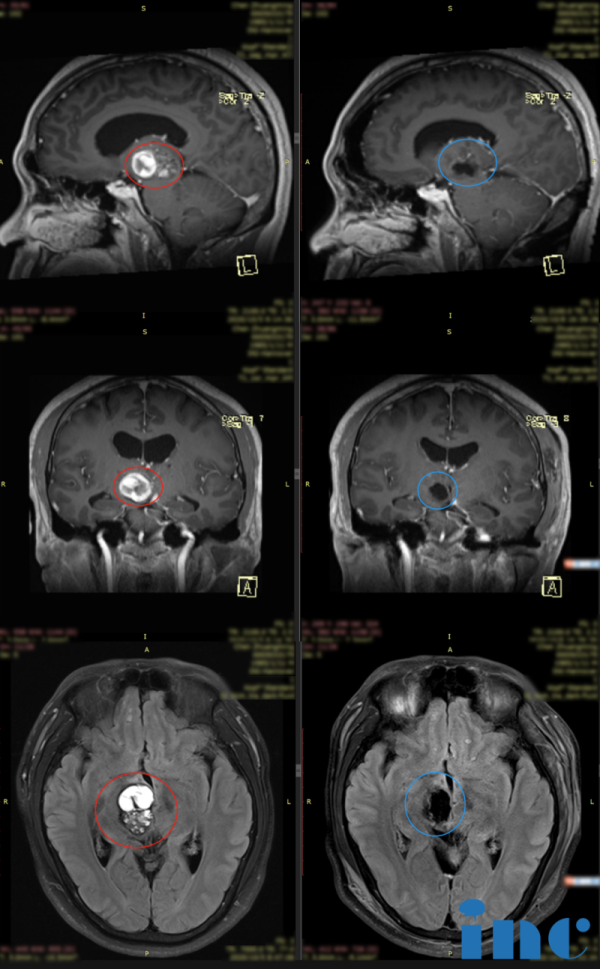

患者情况:M先生,44岁,因左侧肢体无力走不稳路而检查出中脑腹侧较大占位,压迫丘脑。后被确诊为“脑干海绵状血管瘤”。

术后二天:复查CT显示,病变占位全部切除,未见病变残留,术腔及周围无出血,无水肿,无占位效应,周边脑组织自然复位,开颅骨瓣复位好。MRI检查证明脑干海绵状血管瘤得到全切,无新发脑损伤,副鼻窦结构及气腔形态正常。引流管已拔除。